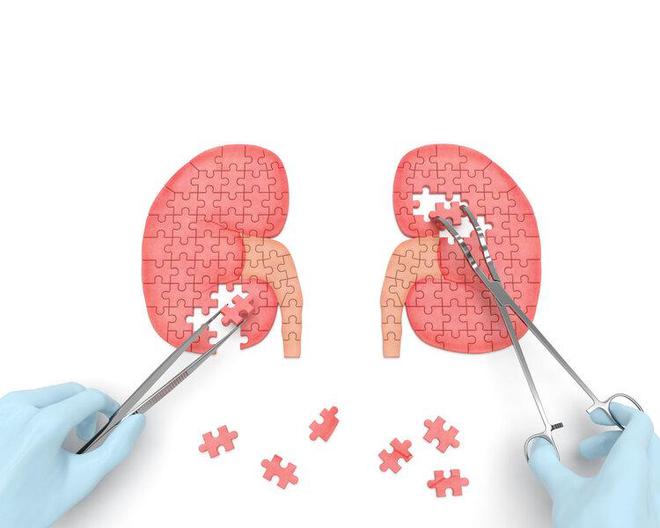

一、尿毒症的发生并非“突如其来”

数据显示,我国慢性肾病的患病率在10.8%左右,患病人数超过1.5亿人次,而在这些慢性肾病患者中,每100个就有一个会发展成尿毒症。

临床上将慢性肾病按损伤程度不同分为1~5期,其中1期的患者一般没有明显症状,但会存在尿液异常表现;2期患者则可能有蛋白尿、尿潜血以及尿pH值异常的症状。

3期的患者会开始出现乏力、水肿、血尿以及贫血等全身症状;4期患者为严重肾功能不全者,身体有纳差、钙磷钾代谢异常、高血压等表现。

5期为终末期肾病,也就是我们所说的尿毒症,患者会有心功能不全、高钾血症、代谢性酸中毒等危及生命的并发症出现。

从1期发展到5期并非一蹴而就,中间需要经历很长的一个过程。

三、得了慢性肾脏病,最终“归宿”是尿毒症?

尿毒症多是由于慢性肾病演变而来,那是否说明罹患慢性肾病最终的结局一定是尿毒症呢?答案是否定的。

罹患慢性肾病后,积极进行干预治疗,可以有效延缓甚至是逆转肾功能恶化。